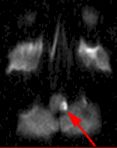

Fig. 1 Fig. 2 Fig. 3 Fig. 4

MRI Findings: In the supratentorial regions, some atrophy and chronic small vessel deep white matter ischemic changes were observed (Fig. 1) but no acute lesion or infarct was observed on MR diffusion. In the posterior fossa, however, a subtle small 1 cm hyperintensity can be seen in the left side of medulla on T2 weighted (Fig. 2) and FLAIR images (Fig. 3). This can be seen with an infarct, but its age would remain indeterminate. The MR diffusion image (Fig. 4) shows hyperintensity in the same region consistent with an acute infarct (arrows) as opposed to chronic ischemic changes.

Final Diagnosis: Based on the MR appearance, diagnosis of acute lateral medullary infarct was provided. This is a classic appearance of a posterior inferior cerebellar artery (PICA) infarct (PICA Syndrome), which may have thrombosed.